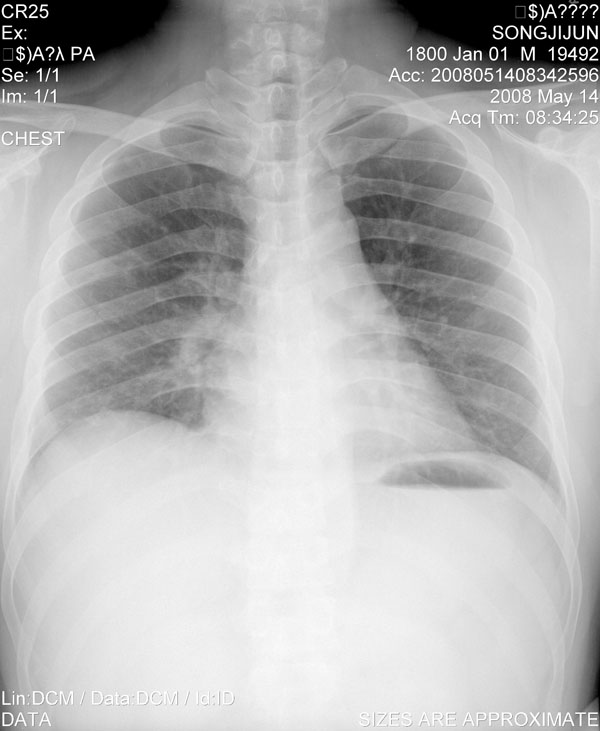

一周后复查胸片基本正常

经一周抗炎抗病毒治疗复查胸片示病变大部吸收,基本恢复正常,未做气管镜检查,考虑为炎性变或霉菌感染。